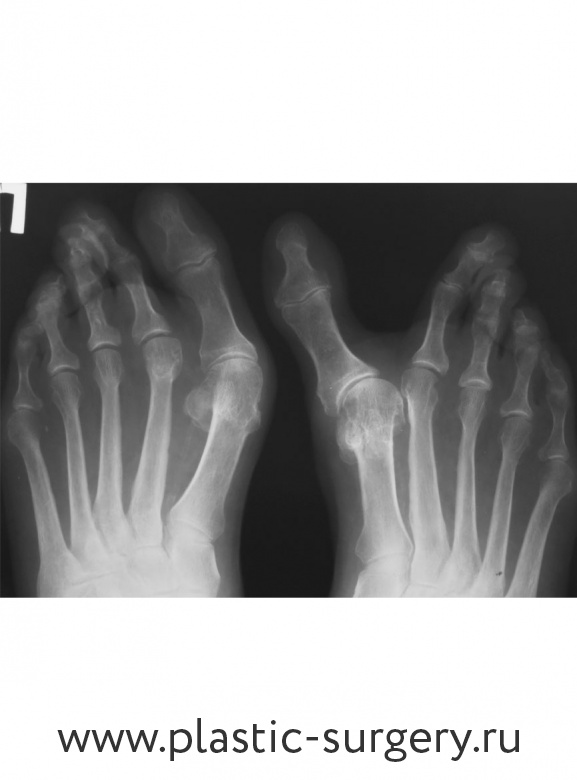

Михаил Наумович вспоминает: «К нам обратилась молодая и интересная женщина. Жить да жить, получать удовольствие от жизни… А без ног мы плохо живем. У пациентки была вторая степень деформации, граничащая с третьей. То есть вовлечены все отделы стопы. Проблема мешает ходить — из-за боли формируются натоптыши и молоткообразные пальцы».

Была проведена операция по коррекции вальгусной деформации стопы.

Поперечное плоскостопие III степени, вальгус 1-го пальца стопы, молоткообразная деформация 2-5-го пальца, варусная деформация 5-го пальца. Лечение: малоинвазивная реконструкция переднего отдела обеих стоп. Фото - через 6 мес. после операции.

Поперечное плоскостопие III степени, вальгус 1-го пальца стопы, варусная деформация 5-го пальца, молоткообразная деформация 2-5-го пальца. Лечение: малоинвазивная реконструкция переднего отдела обеих стоп.